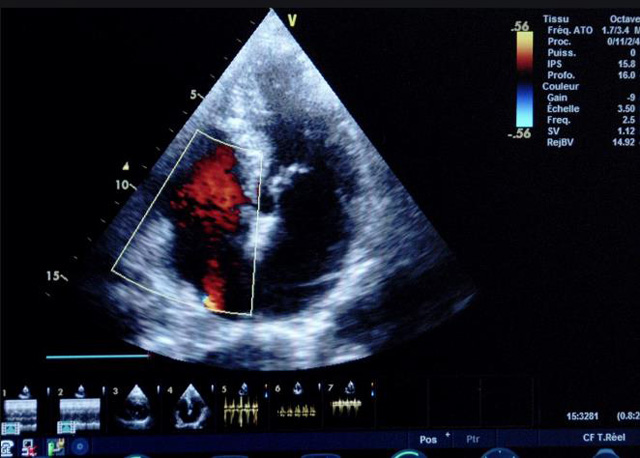

二、彩色室壁運(yùn)動分析

(一)基本原理彩色室璧運(yùn)動分析,從整體散射數(shù)據(jù)中識別心內(nèi)膜邊界,并與前一幀彩色不同,心臟收縮或舒張期開始到結(jié)束時心內(nèi)膜的全部過程。每一次順序顯示結(jié)束后,原來的彩色自動消失,以便進(jìn)入下一個顯示過程。其結(jié)果是獲得對應(yīng)于每一個心動周期的彩色顯示,描繪特定周期內(nèi)室壁運(yùn)動的時間運(yùn)動軌跡。

(二)操作步驟根據(jù)背向散射數(shù)據(jù)中將心內(nèi)膜運(yùn)動的位移過程分類為組織或血液的原理,邊緣檢測跟蹤心內(nèi)膜和血液的界面。橙色表示收縮期的開始,收縮期不同時相逐幀顯示色彩均疊加在收縮末期最后一幀圖像中。檢查時,可按以下步驟進(jìn)行:

①顯示較為理想的二維圖像,常用切面有心尖四腔心、二腔心、左心室長軸和左心室乳頭肌水平短軸切面。

②啟動AQ系統(tǒng),啟動后適當(dāng)?shù)卣{(diào)節(jié)增益補(bǔ)償,顯示心內(nèi)膜。

③啟動CK系統(tǒng),啟動后劃定感興趣區(qū)域。同時記錄的心動圖R波頂點(diǎn)為舒張末期,T波終點(diǎn)為收縮末期,顯示RT間期的CK彩階圖,連續(xù)記錄3~ 5個心動周期。

④對所獲圖像和數(shù)據(jù)進(jìn)行分析和計算。

(三)檢測節(jié)段性室壁運(yùn)動異常,研究冠心病患者左心室功能和分析局部室壁運(yùn)動過程中。測量每一節(jié)段室壁的運(yùn)動量,運(yùn)動正常的節(jié)段彩帶色彩均勻?qū)哟喂庹_\(yùn)動減弱的節(jié)段,厚度薄層次不全。心內(nèi)膜位移幅度和速度均減低。心內(nèi)膜位移幅度和速度甚低或難以測得。正常的多層彩帶消失,呈現(xiàn)紅色色帶,心內(nèi)膜位移呈負(fù)向,幅度和速度亦減低。急性心肌梗死的患者中可用于識別存活心肌抑或壞死心肌。多巴酚丁胺負(fù)荷試驗存活心肌的心內(nèi)膜位移幅度增高,停藥后即消失,而壞死心肌則無上述表現(xiàn)。實時檢查冠心病的節(jié)段性室壁運(yùn)動異常,有時候通過發(fā)現(xiàn)局部心肌運(yùn)動的時相異常,對于心臟傳導(dǎo)障礙的診斷也可能有幫助。